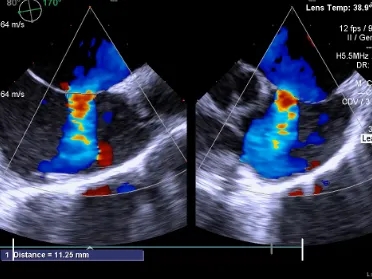

经食道超声所见:房间隔总长度约41mm。房间隔中部局部呈瘤样向右房膨出范围约11×19mm,房间隔中部回声中断约11×9mm,缺损上缘距房顶约17mm,缺损下缘距二尖瓣约10mm,缺损后下缘距下腔静脉约21mm,缺损后上缘距上腔静脉约13mm,短轴切面前残端0mm,后残端24mm。

CDFI示:房水平左向右分流。上、下腔静脉回流入右房正常。冠状静脉窦未见扩张。

超声提示:房间隔缺损(II孔型),房间隔膨胀瘤形成。

测量膨出瘤基底宽19.61mm,深7.00mm

房间隔总长44.22mm,缺损大小14.80mm

超声可见房间隔连续中断,彩色多普勒可见过隔血流